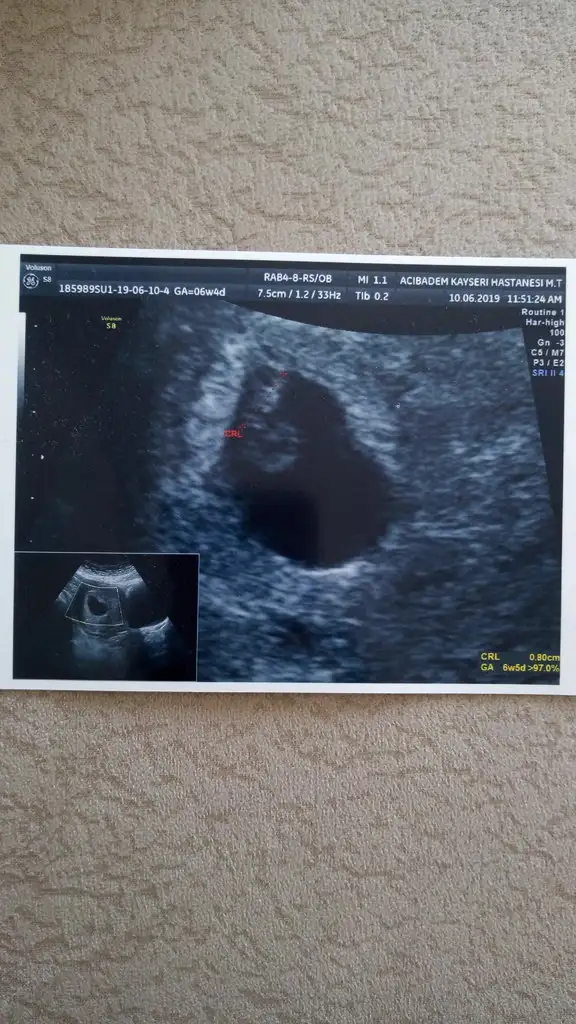

Bu dogrumu canm benim 7 haftalik teoriye solda karinda erkek zaten gissedyrdm dr birgun onceerkek ikili testte kiz dedi anlamadk 14 haftalgm ins degsr9+4 göre erken sekil almış erkek diyorum

12 hafta usg varmıBu dogrumu canm benim 7 haftalik teoriye solda karinda erkek zaten gissedyrdm dr birgun onceerkek ikili testte kiz dedi anlamadk 14 haftalgm ins degsr

Yok tek 14 haftalik var iste cnm ama 7. hqftalikta ultrason kagidana gore erkek net belli yarn atarm erkek hissedyrm hep icimde ama anlamadm10 yada 11